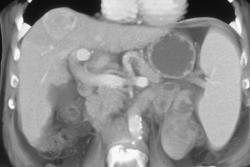

Metastatic Renal Cell Carcinoma to Liver and Portocaval Nodes